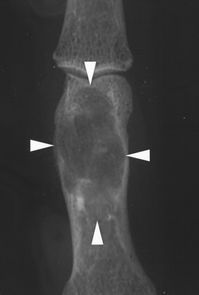

骨巨细胞瘤往往影响20岁以上的患者,其发病高峰发生在生命的第三个十年[1]。患者通常会出现疼痛。在放射学上,病变多显示中央或偏心性溶骨性破坏,并侵及干骺端,可完全破坏软骨下骨质,一般情况下,病变边界较清楚,呈膨胀性改变,其内可见纤细骨嵴,呈“分叶状”或“皂泡样”改变,部分病例可没有膨胀性改变,肿瘤可破坏或突破骨皮质,进入周围软组织,形成软组织内肿块,骨膜反应一般不存在,常可伴有病理性骨折,位于骶骨的骨巨细胞瘤,病变往往是偏心性,且常累及一侧骶髂关节。大多数人都有明确的但非硬化的边缘(图1A)。少数(10-20%)具有较少明确的边缘(图1B),并且硬化边缘很少(图1C)。

图1A-47岁女性,巨细胞瘤。X线可见腓骨近端没有硬化边缘的透亮区。

图1B -37岁女性,巨细胞瘤。股骨远端边缘(箭头)边缘不清。

图1C-19岁女性,巨细胞瘤。显示胫骨近端干骺端和骨骺有硬化边缘(箭头)。